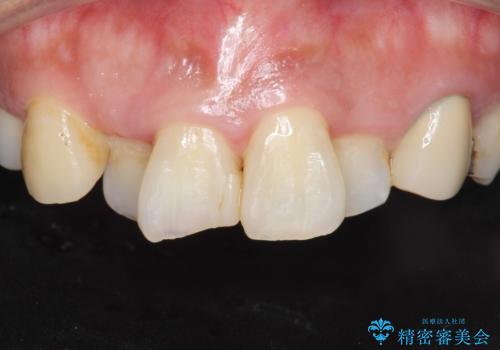

前歯が気になる。ブリッジによる治療。

- 前歯のがたつきが気になるとの事で来院。

①矯正を行う(費用と時間がかかる)

②左右2番の歯を抜歯してブリッジの被せ物を入れる(矯正ほど費用、時間はかからない)

という計画を立てて患者様に選んでもらいました。

②の方を選択されましたので被せ物治療を行いました。